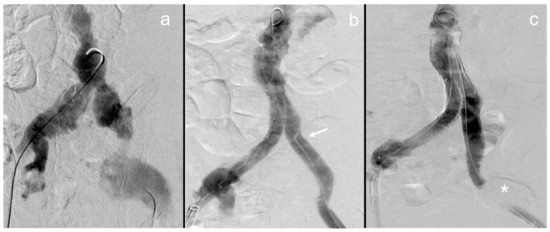

3.2. Case Descriptions

2.2. Interventional Technique